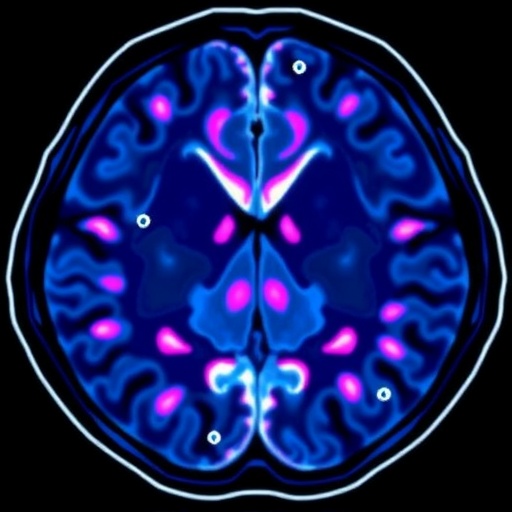

Radiomics, the high-throughput extraction of quantitative features from medical images, transforms standard MRI scans into complex datasets reflecting tumor heterogeneity, texture, shape, and intensity variations. These multidimensional signatures can correlate with underlying genetic alterations such as EGFR mutations. By systematically aggregating data from thirteen studies encompassing 2369 metastatic NSCLC cases, the authors rigorously evaluated the diagnostic performance of MRI radiomics in this context.

Technically, radiomics harnesses sophisticated image processing algorithms to extract features such as histogram-based intensity metrics, texture analysis measures like gray-level co-occurrence matrices, and morphological characteristics. Machine learning models then integrate these features to classify mutation status with increasing accuracy. The reviewed studies utilized diverse MRI sequences, including T1- and T2-weighted images, emphasizing the adaptability of radiomics across imaging protocols.